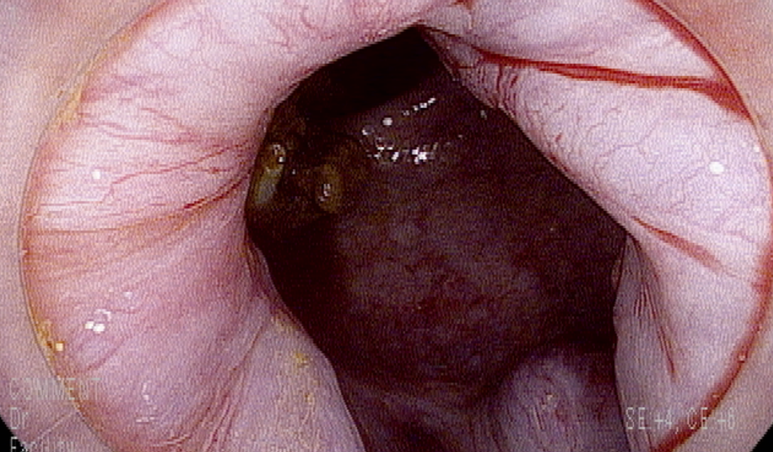

직장경 시행

직장에 변은 정상변으로 혈과 섞이지 않아 하부 직장 출혈임을 시사함.

내치핵 변화도 있으나 최근 출현한 흔적은 없음